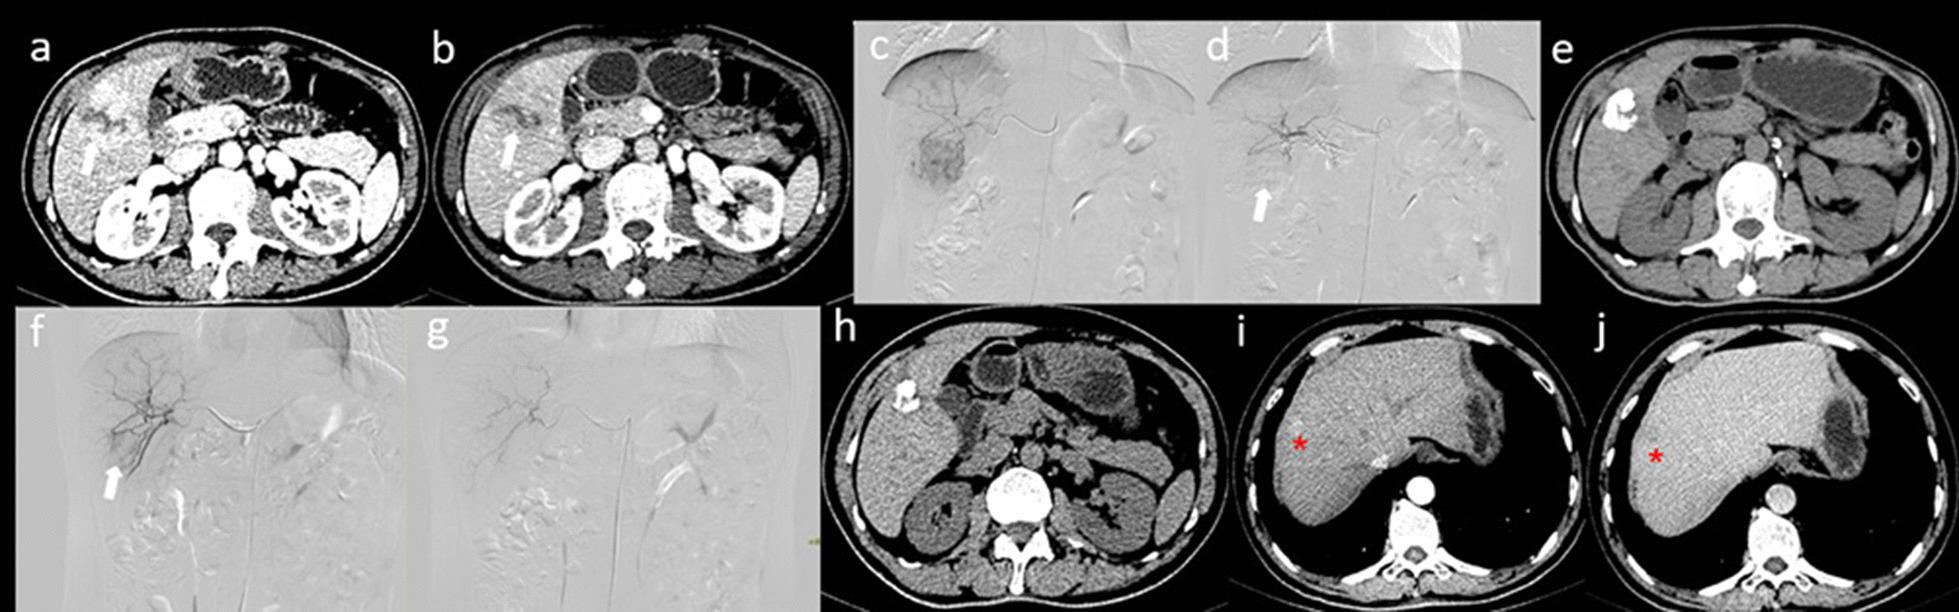

在一项为期10年的单中心比较研究中,序贯性经动脉化疗栓塞术和早期射频消融术可改善早期-中期肝细胞癌的临床结局。

Sequential transarterial chemoembolization and early radiofrequency ablation improves clinical outcomes for early-intermediate hepatocellular carcinoma in a 10-year single-center comparative study.

Transarterial chemoembolization (TACE) and radiofrequency ablation (RFA) are effective treatment methods for unresectable hepatocellular carcinoma (HCC). However, there is still a lack of clinical research on whether early sequential RFA, compared with late combination therapy, can improve the long-term efficacy of initial TACE treatment.

METHODS

This retrospective study investigated a cohort of patients who underwent combination therapy using TACE and RFA (TACE followed by RFA) from January 2010 to January 2020 at our medical centre. A total of 96 patients underwent TACE combined with early RFA (usually during the first hospitalization), which was called TACE + eRFA. Thirty-four patients received 1-2 palliative TACE treatments first and then underwent TACE treatment combined with late RFA (TACE + lRFA). All patients continued to receive palliative TACE treatments after intrahepatic lesion progression until reaching intolerance. The overall survival (OS) rate, time to tumour progression (TTP), tumour response rate and major complication rates were compared between the two groups.

RESULTS

There were significant differences in the median OS (46 months vs 33 months; P = 0.013), median TTP (28 months vs 14 months; P < 0.00), objective response rate (ORR) (89.6% vs 61.8%, P = 0.000) and disease control rate (DCR) (94.8% vs 73.5% P = 0.002) between the two groups. Multivariable analysis revealed that the Barcelona Clinic Liver Cancer stage was an independent risk factor for OS. Meanwhile, multivariable analysis revealed that TACE + eRFA was associated with an enhanced TTP.

CONCLUSION

Early sequential RFA treatment in patients with early-intermediate HCC can improve local tumour control and clinical outcomes while reducing the frequency of TACE treatment. In clinical practice, in HCC patients initially treated with TACE, it is recommended to combine RFA as soon as possible to obtain long-term survival.